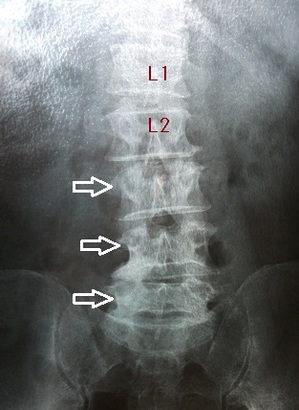

腰部レントゲン側面像 腰部レントゲン正面像

すぐに同僚が近くの病院へ連れて行ってくれました。レントゲン撮影の結果、第3、4、5腰椎の圧迫(多発)骨折が

判明致しました。多発骨折とは、同時に2つ以上の骨が骨折することを言います。(左右上画像の矢印)

左右上画像の第1腰椎(L1),第2腰椎(L2)と比較すると、椎体の前面がくさび形に、あるいは椎体全体が圧潰されて

変形してしまいます。